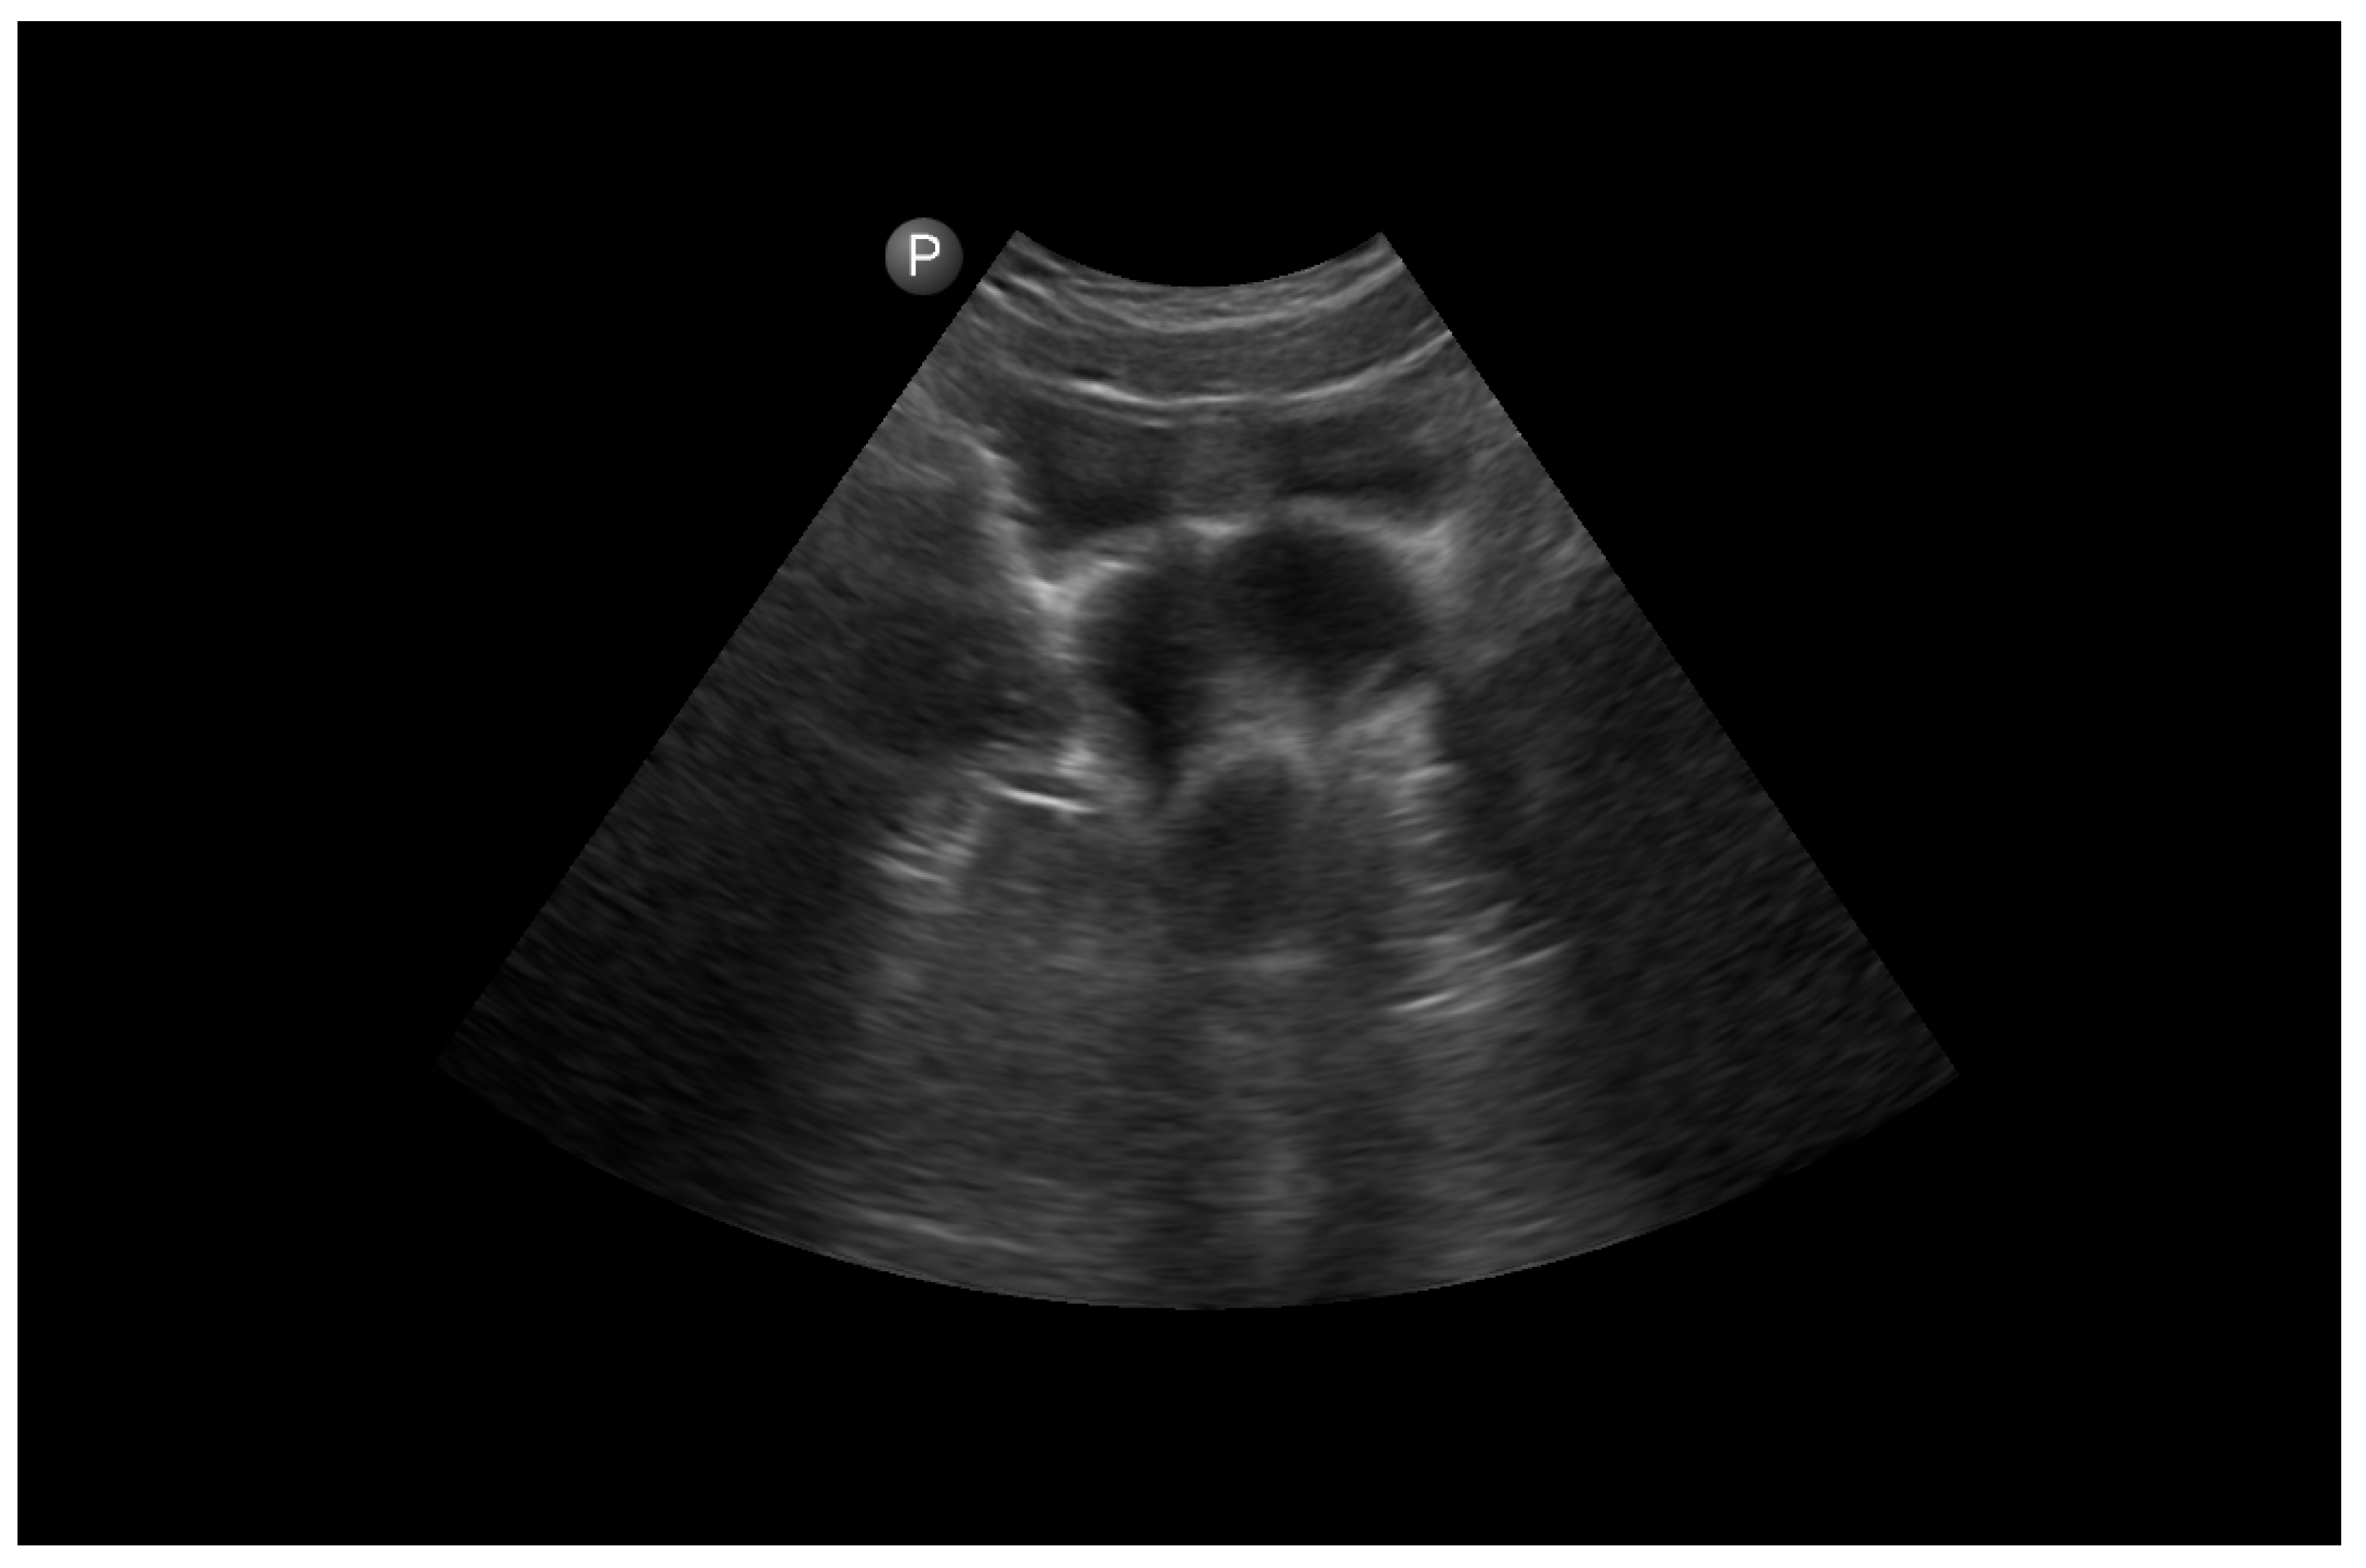

2.2. Preoperative Management